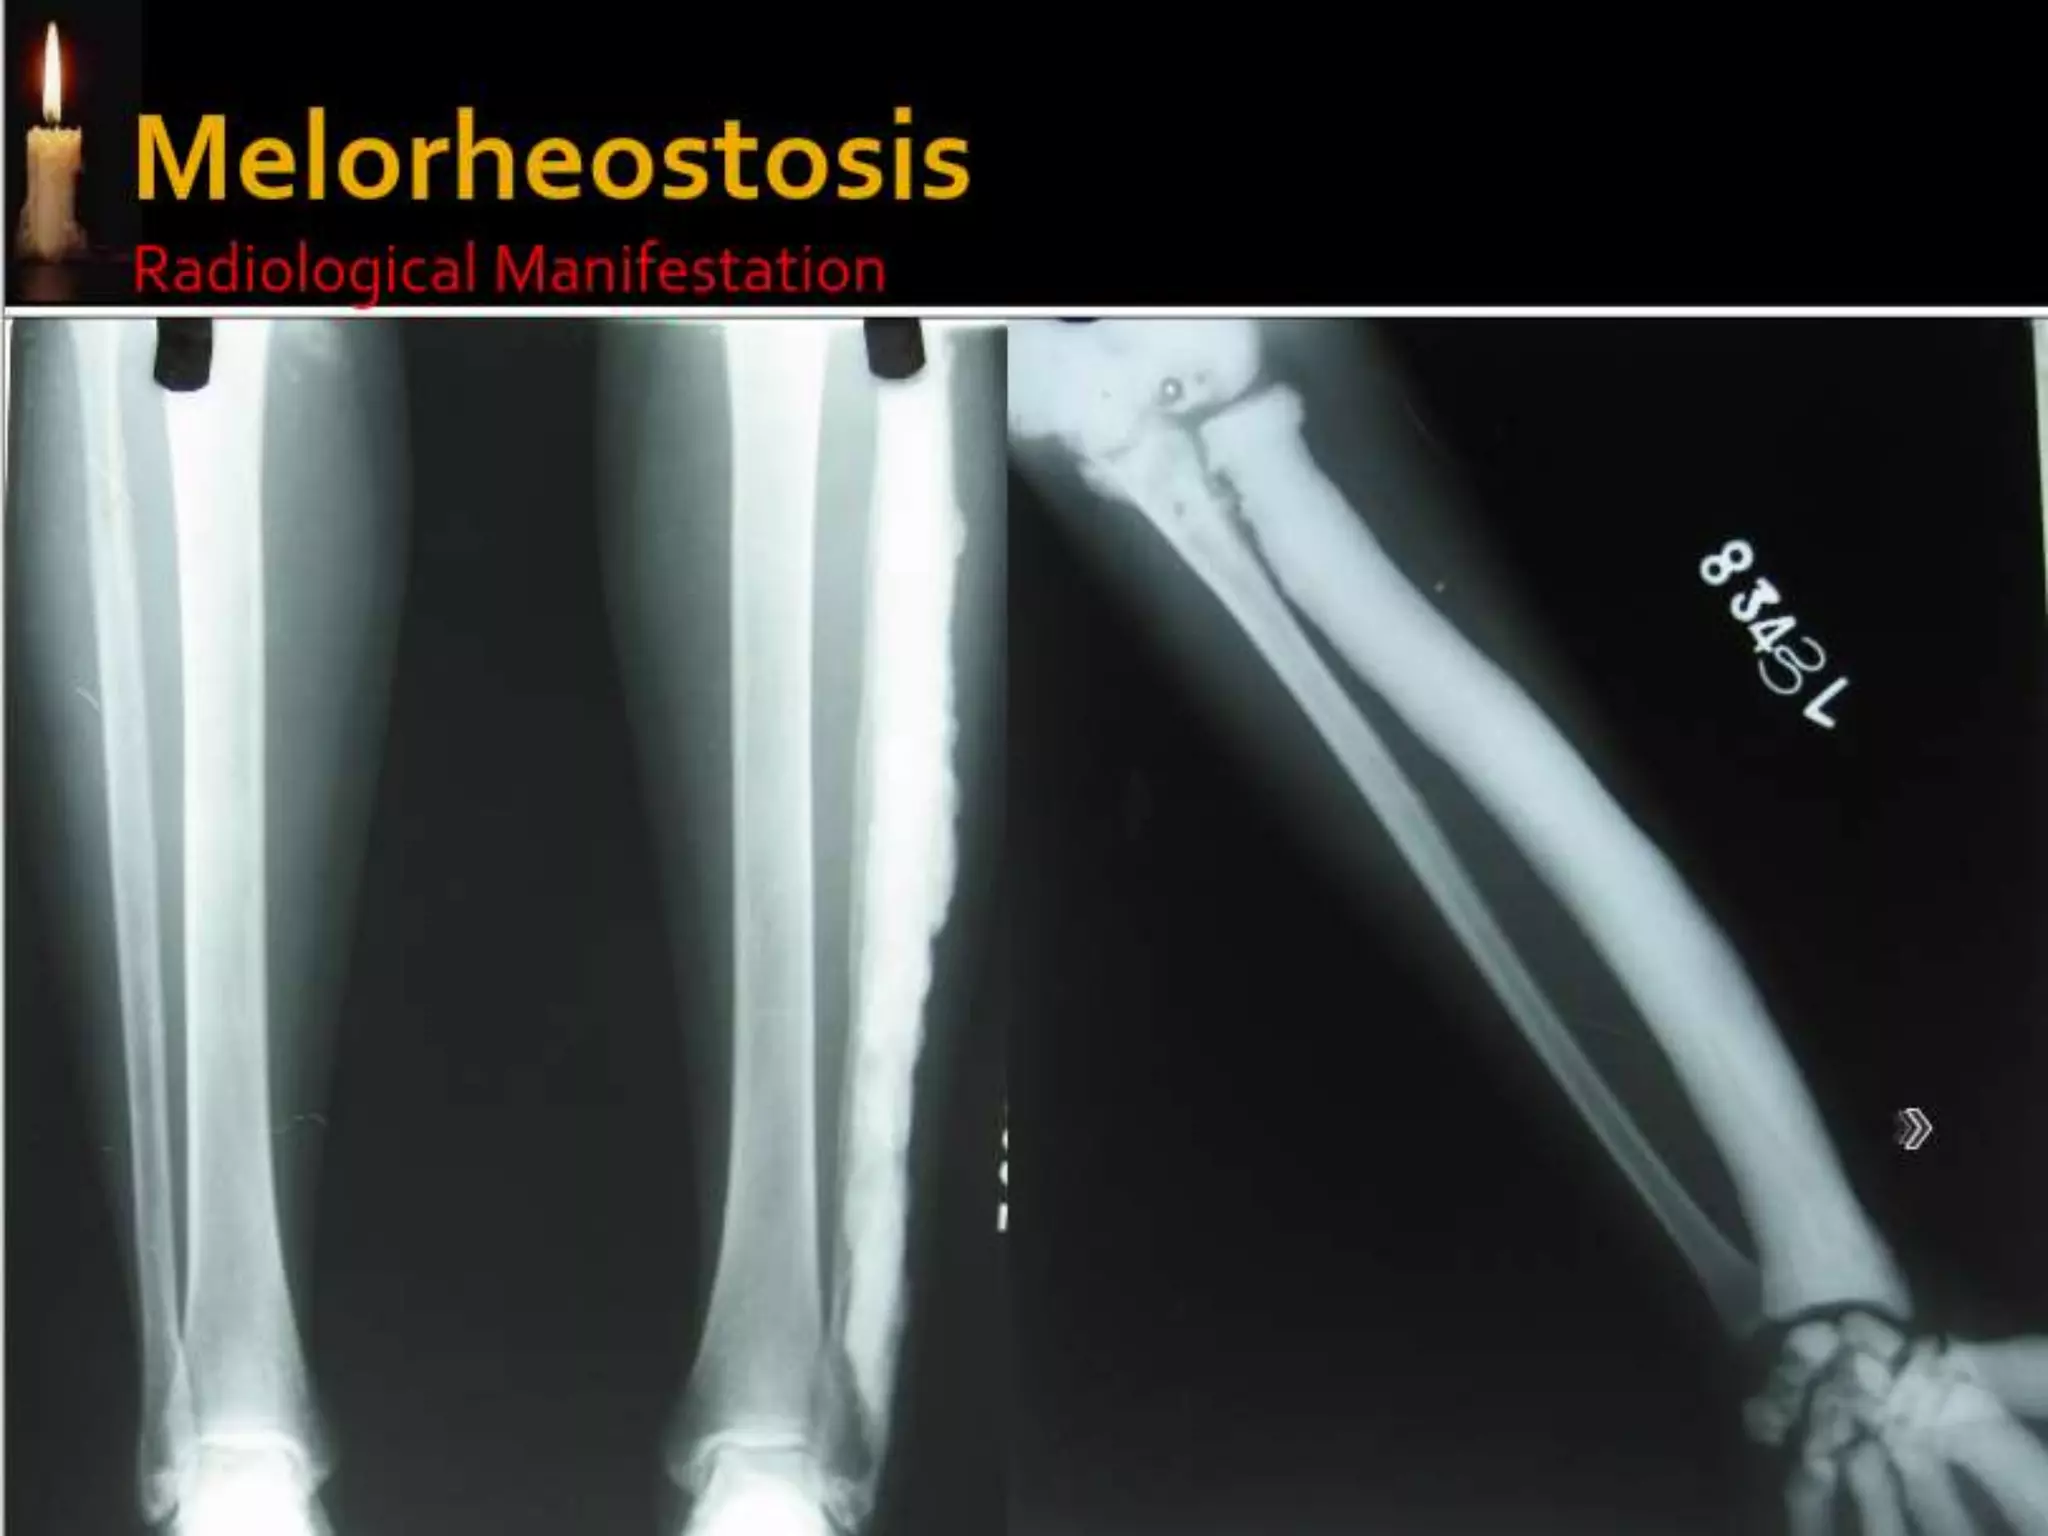

Osteopoikilosis is a benign, autosomal dominant sclerosing

dysplasia of bone characterized by the presence of numerous bone

islands in the skeleton.

The radiographic appearance of osteopoikilosis on an x-ray is

characterized by a pattern of numerous white densities of similar

size spread throughout all the bones. This is a systemic condition. It

must be differentiated from blastic metastasis, which can also

present radiographically as white densities interspersed

throughout bone. Blastic metastasis tends to present with larger

and more irregular densities in less of a uniform pattern. Another

differentiating factor is age, with blastic metastasis mostly

affecting older people, and osteopoikilosis being found in people

20 years of age and younger.

Men and women are affected in equal number. ,reflecting the fact

that this disease attacks indiscriminately. Additionally, the disease

is often associated with melorheostosis, despite the apparent lack

of correlation between Melorheostosis and genetic heritability

Osteopoikilosis is abenign, autosomal dominant sclerosing dysplasia of bone characterized by the presence of numerous bone islands in the skeleton. The radiographic appearance of osteopoikilosis on an x-ray is characterized by a pattern of numerous white densities of similar size spread throughout all the bones. This is a systemic condition. It must be differentiated from blastic metastasis, which can also present radiographically as white densities interspersed throughout bone. Blastic metastasis tends to present with larger and more irregular densities in less of a uniform pattern. Another differentiating factor is age, with blastic metastasis mostly affecting older people, and osteopoikilosis being found in people 20 years of age and younger. Men and women are affected in equal number. ,reflecting the fact that this disease attacks indiscriminately. Additionally, the disease is often associated with melorheostosis, despite the apparent lack of correlation between Melorheostosis and genetic heritability